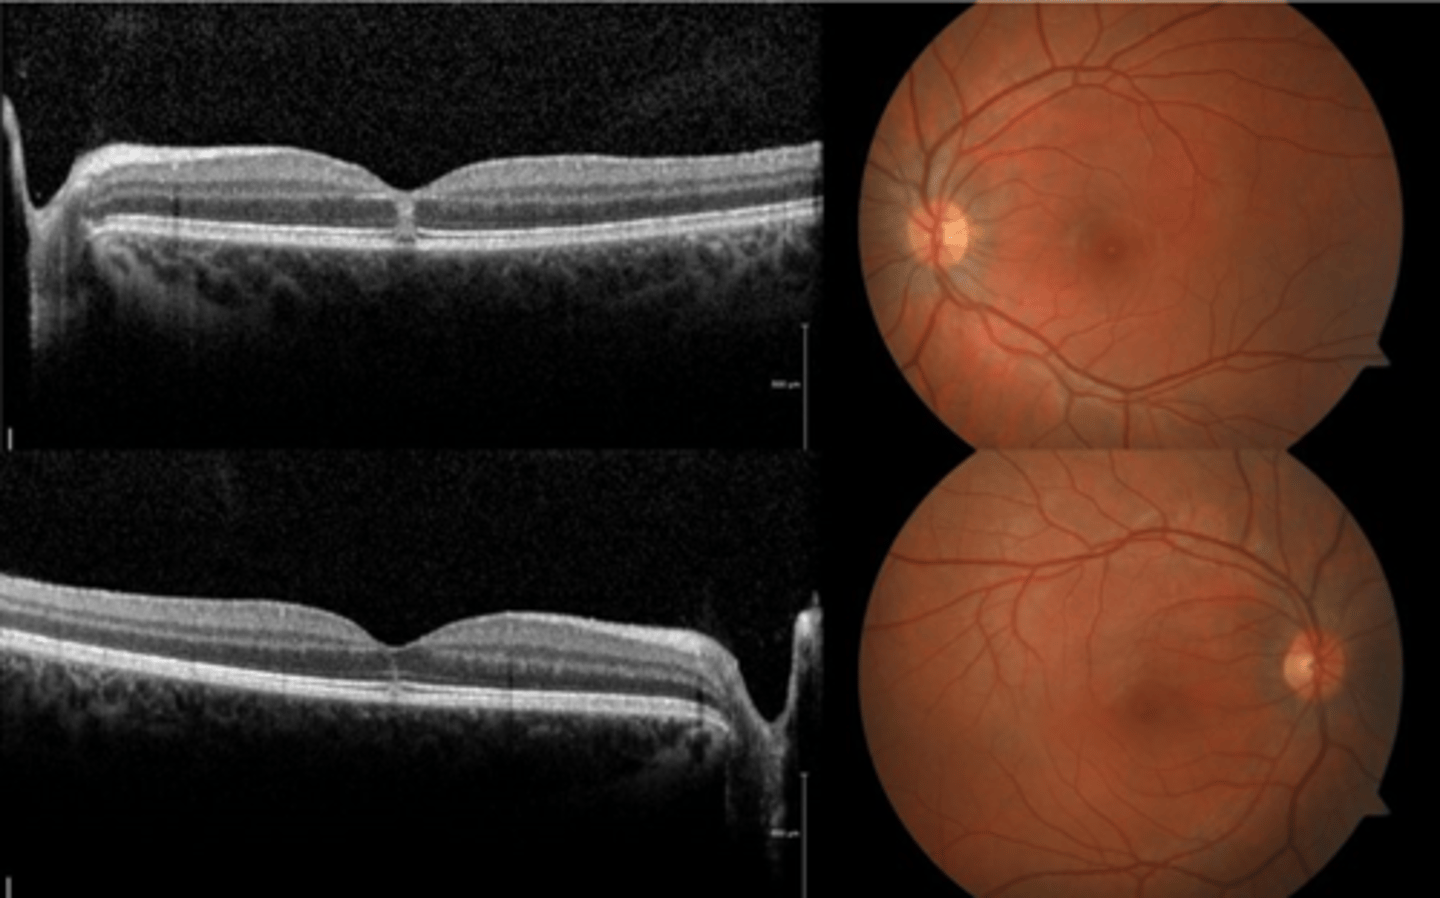

How does choroidal rupture appear on OCT here?

loss of RPE continuity at site of rupture = inner choroid atrophy

How does choroidal rupture appear on OCT here?

RPE disruption

+/- hemorrhage